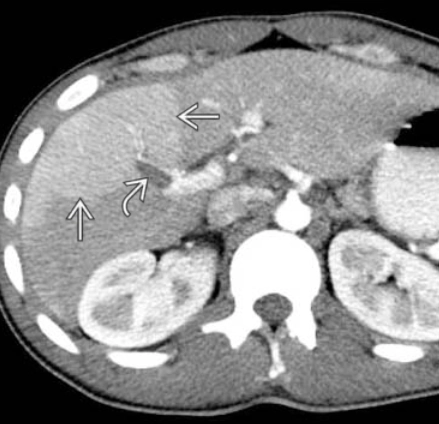

• Shunt động- tĩnh mạch cửa trong gan (Intrahepatic arterioportal shunt)

• Tăng áp lực tĩnh mạch cửa (Portal Hypertension)